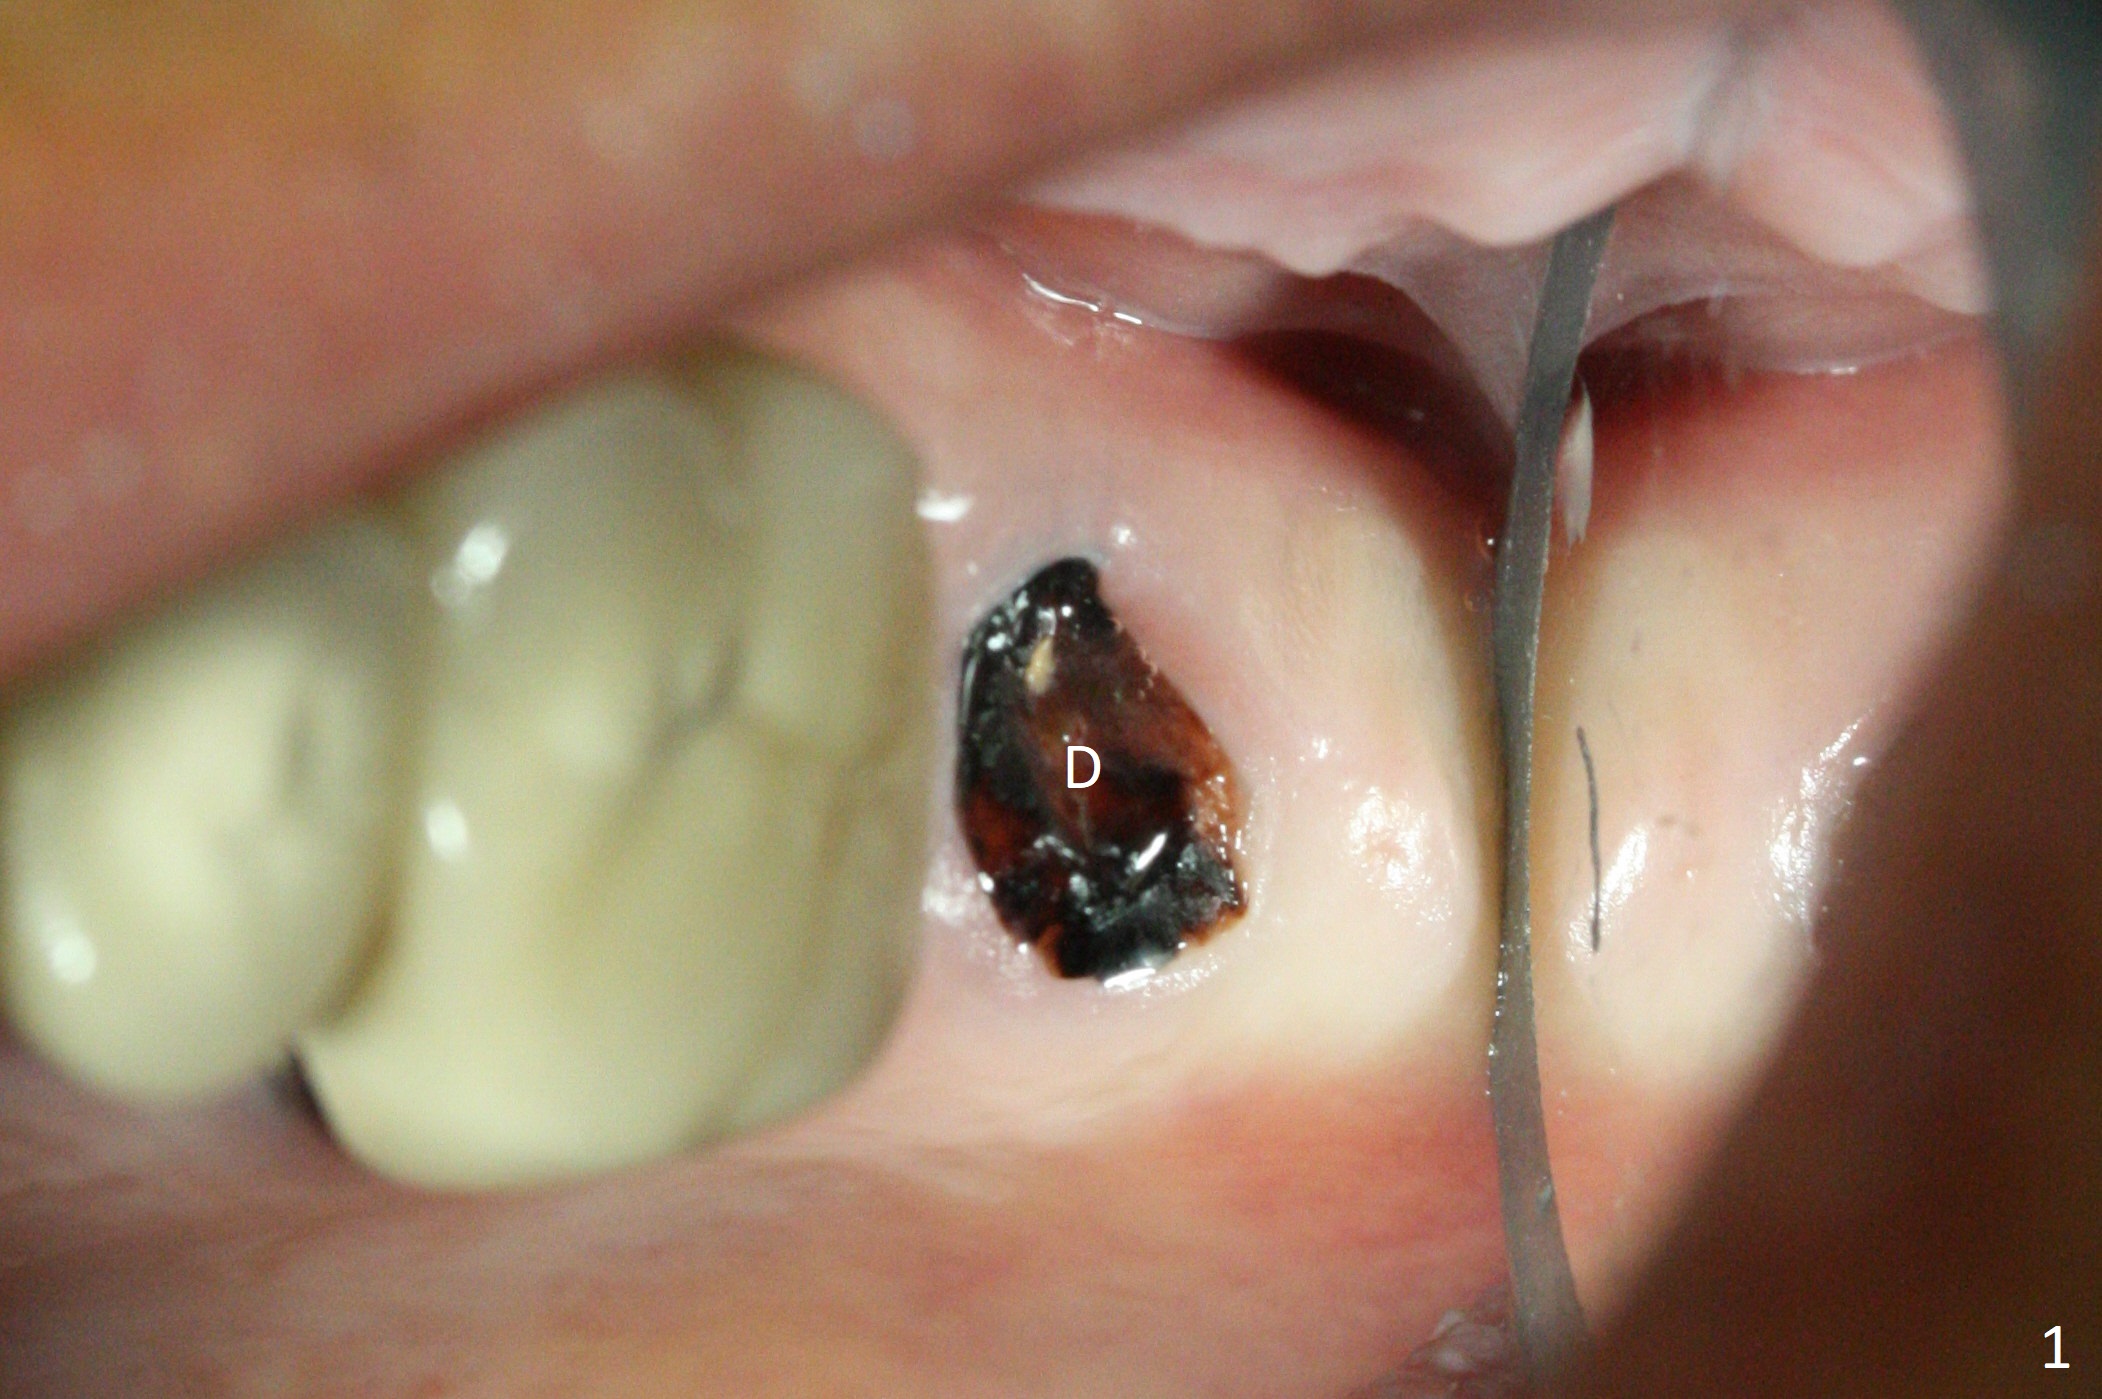

After removal of the mesial (M) and distal (D) residual roots of the tooth #15 (Fig.1,2), Magic Split is used to test bone density (high), followed by Magic Drills from Magic Sinus Lift Kit (for 4 mm) and Magic Surgical Kit (for 5 mm). It appears that the sinus floor has been perforated with the intact sinus membrane. Following minimal use of Magic Lifter, Vanilla Graft is inserted (Fig.3,4 *) and a 4x9 mm dummy implant is placed. After placement of more allograft (Fig.5 *), a 5x7 mm implant is placed with ~ 35 Ncm. With placement of a 5.5x4(2) mm abutment, an immediate provisional is fabricated to close the socket. Six months postop, the bone graft remains in the sinus around the apical end of the implant (Fig.6 *), while there seems no bone loss coronally (Fig.7). In fact there is, as shown later (Fig.8-11 < and lingual (L)). The crown is recemented 6 months post cementation (due to short abutment). The abutment seems to be incompletely seated. When the crown at #14 is reprep following #13 implant, the abutment screw is being untightened, the crown dislodges first. The abutment is confirmed short with more than enough occlusal clearance. After use of 5.5 and 6.0 mm bone profile drills, a 5x4(3) mm abutment is placed with complete seating.